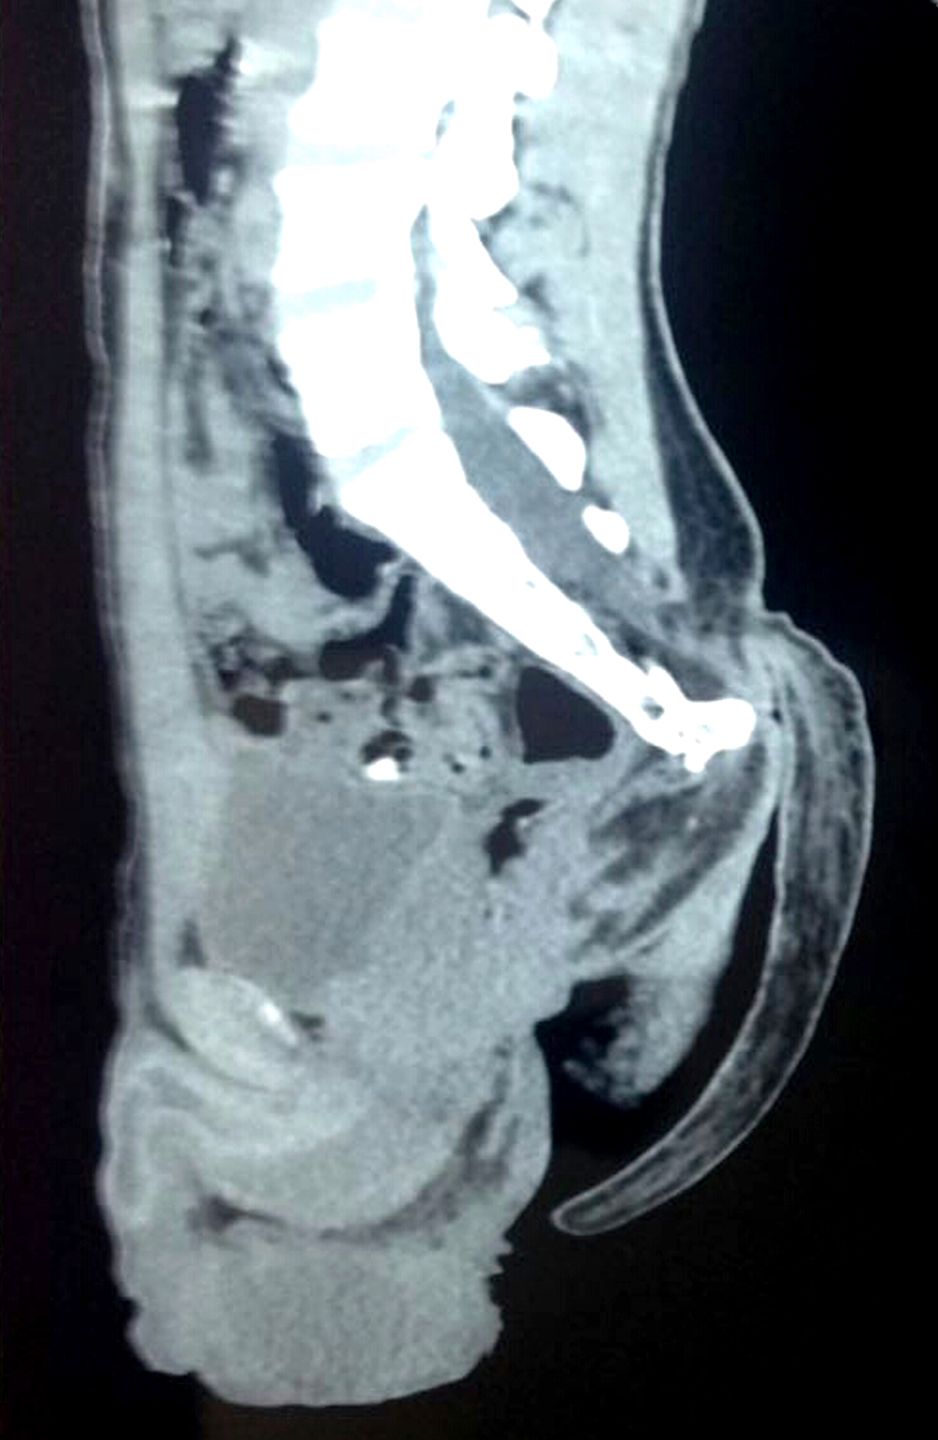

Zespół sześciu lekarzy przeprowadził godzinną operację. Zabieg zakończył się sukcesem i pacjent może opuścić szpital po tygodniu. Sprawę ułatwił fakt, że w ogonie nie było kości, a jedynie naczynia krwionośne i tkanki miękkie. Wśród nielicznych znanych przypadków urodzeń z ogonem było kilka takich, gdzie wewnątrz była kość.

Osiemnastolatek z Nagpuru w Indiach przyszedł do szpitala skarżąc się na bolesną "narośl" na plecach. To jeden z tych rzadkich przypadków, kiedy ogon nie zanikł na etapie ciąży. Rodzina, bojąc się stygmatyzacji, nie poddała go operacji zaraz po porodzie, tylko ukrywała ogon przed światem. On sam chował go w spodnie, gdy siadał, co sprawiało mu duży dyskomfort.

Z czasem ogon stał się poważnym problemem, bo nastolatek miał problemy z siedzeniem i spaniem.